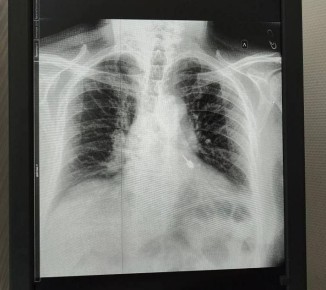

Состояние больного оценивалось как крайне тяжёлое. Он получил серьёзный перелом грудной клетки, за грудиной образовалась гематома. Скопление крови в плевральной полости нарушало дыхание и работу сердечно-сосудистой системы. Ситуацию осложняла сопутствующая патология - аневризма аорты.